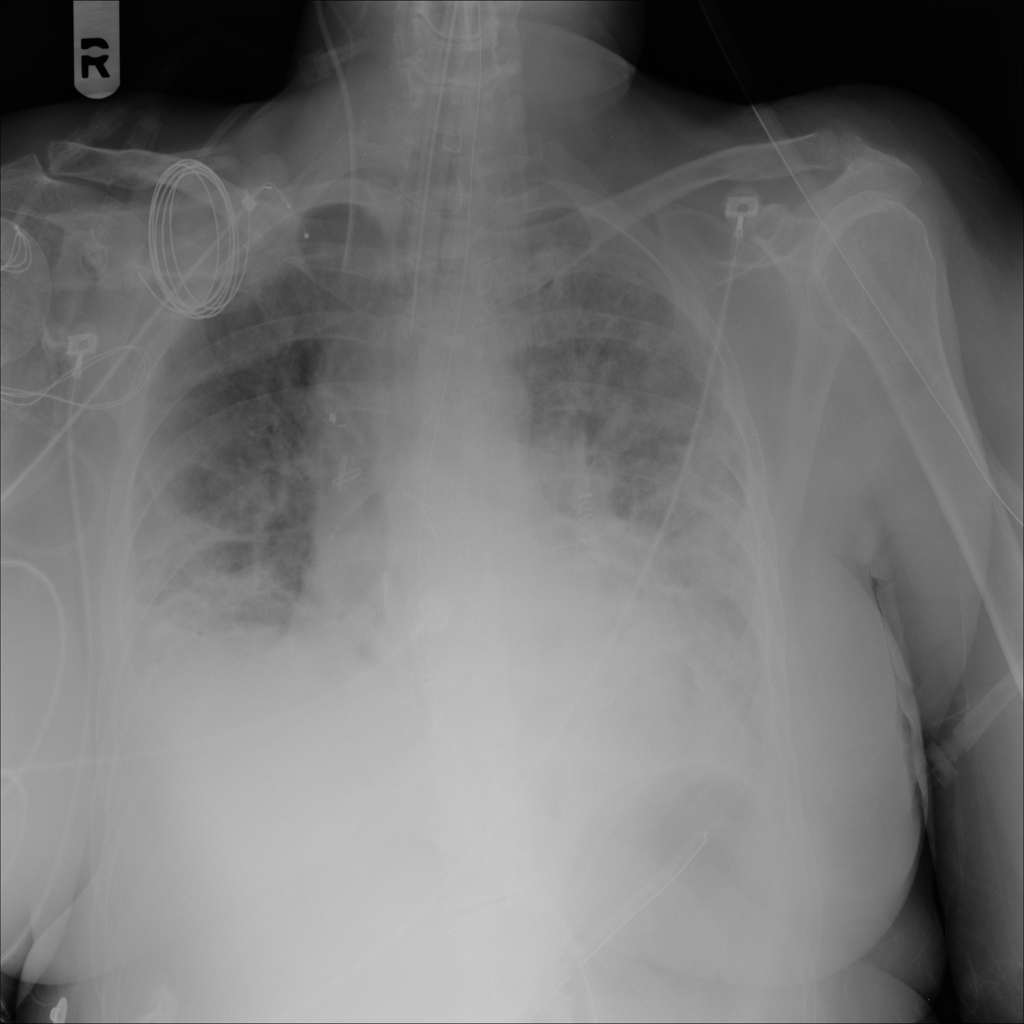

PAT-E81B · IMG-000Effusion

PAT-E81B · IMG-000

PA